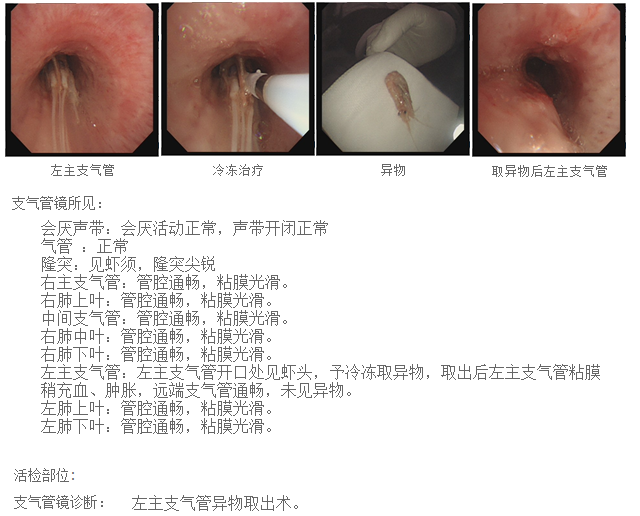

考虑到呛入气管内的白虾体积较大,无法经鼻腔取出,我们为该患者进行了经口气管镜检查。

左主支气管内可见白虾的头部,长长的虾须延升至隆突处

考虑到白虾质地较软,异物钳钳夹过程中可能导致虾头与身体分离、碎裂,导致取出困难,介入团队在商议后决定给患者进行冷冻取异物术。

至此,这只误入歧途的虾,终于被取了出来。